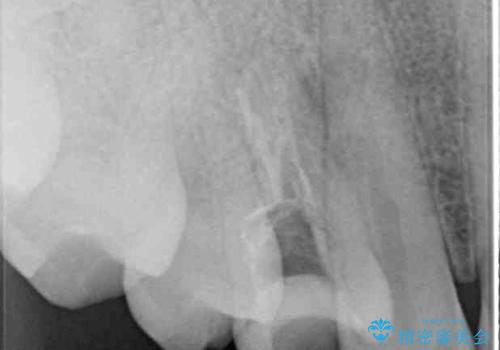

深い虫歯の歯を抜歯 目立つ小臼歯のインプラント治療

- 他院で抜歯が必要と診断され、インプラント治療を希望して来院された患者様です。

口を開けたときに目に付く領域であったので、ジルコニアカスタムアバットメントを用いたインプラント治療を行うこととしました。